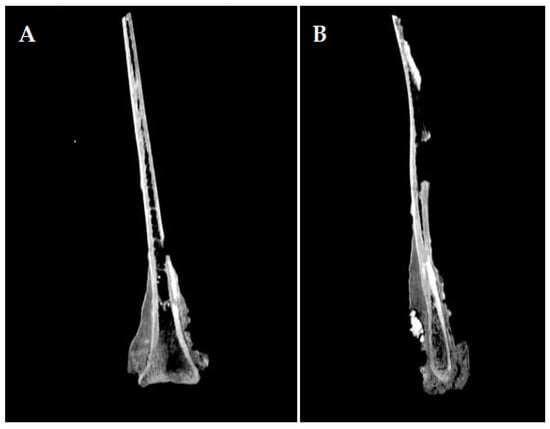

3.2. Description of the Imagistic Investigation

The radiological investigation showed (Figure 2), as expected, just densification of the bony structures around the scapular neck, with no possibility of a clear link to a pathological situation. There is a lack of differentiation among the neighboring structures, such that the supraglenoid tuberosity and its usually much denser structure are hard to tell apart from the surrounding tissue. The borderline between the denser, newly deposited bone is visible also on the radiographic images, especially on the lateral perspective, marking the lateral trajectory of the suprascapular vessels and nerves.

The analysis of the CT images (Figure 3 and Figure 4) indicates a crack that affects the medial blade (which is the broken reconstructed piece), that starts beneath the glenoid cavity, extending along the articular angle, and spanning the entire width of the back’s neck towards the thoracic angle. On the lateral surface, the lack of the dorsal spine can be observed, with the base of the dorsal spine preserved on the cranial edge.

The compact osseous tissue is very well distinguished, both on the lateral side with an average Hounsfield unit of 961, and on the medial side, with an average Hounsfield unit of 1012. The spongy tissue is almost completely absent, with a small presence at the neck level, with an average Hounsfield unit of 98. The spans are visible towards the dorsal edge. These features indicate a limited topical reactive and hypertrophic bony process confined to the superficial level of the compact bone, which did not involve a reactive and proliferative process towards the cancellous core part of the bone.

Figure 4. CT images of the scapula: (A) sagittal section of the scapula displaying the extending tendency of osteophytes and exostoses on the scapula; (B) sagittal section of the scapula showing the hyperostotic bone tissue.